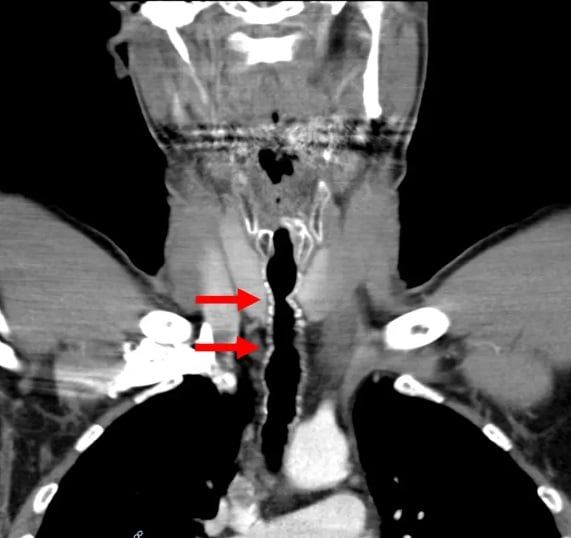

نمو الشعر في حلق الرجل American Journal of Case Reports

الشعر في حلق الرجل American Journal of Case Reports